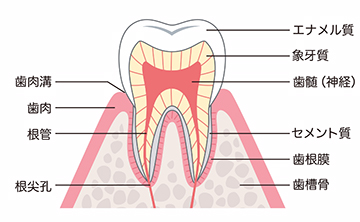

歯の構造

歯の構造は3つからなります

虫歯の前に歯の構造を理解しましょう。歯の構造は、簡単に3層構造から成り立っています。

1. エナメル質は、歯の1番外側になり、人間で言うとヘルメットの役割をします。

2. 象牙質は、人間でいう頭蓋になり、エナメル質に比べると非常に柔らかいです。

3. 歯の神経は、人間でいう脳みそになります。かなり柔かいというかふにゃふにゃになります。

歯の構造を図で表したイメージ図

この歯の周りを歯肉と骨が覆っている形となります。